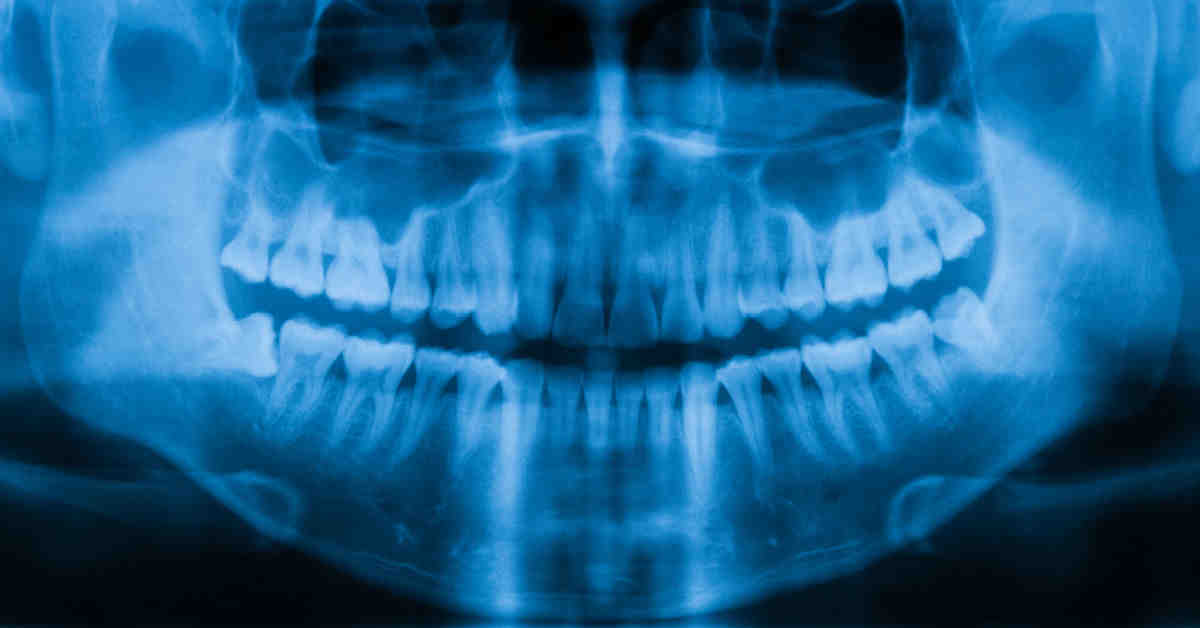

Dental bone grafting is actually a relatively small procedure. Your dentist will make an incision to uncover your jaw bone, then inoculate new bone material with it. This may interest you : Dental Implant Reviews. Your bone creates new bone cells around the grafted material, and builds bone exactly where they need it.

There are several ways dental bone grafting can be done, but the basic procedure is the same: A dentist or oral surgeon makes an incision in the jaw and grafting (sticking) other bone material to the jaw. See the article : Cost Of Dental Implant. Dental bone grafting is usually done if someone has lost one or more adult teeth or has gum disease.